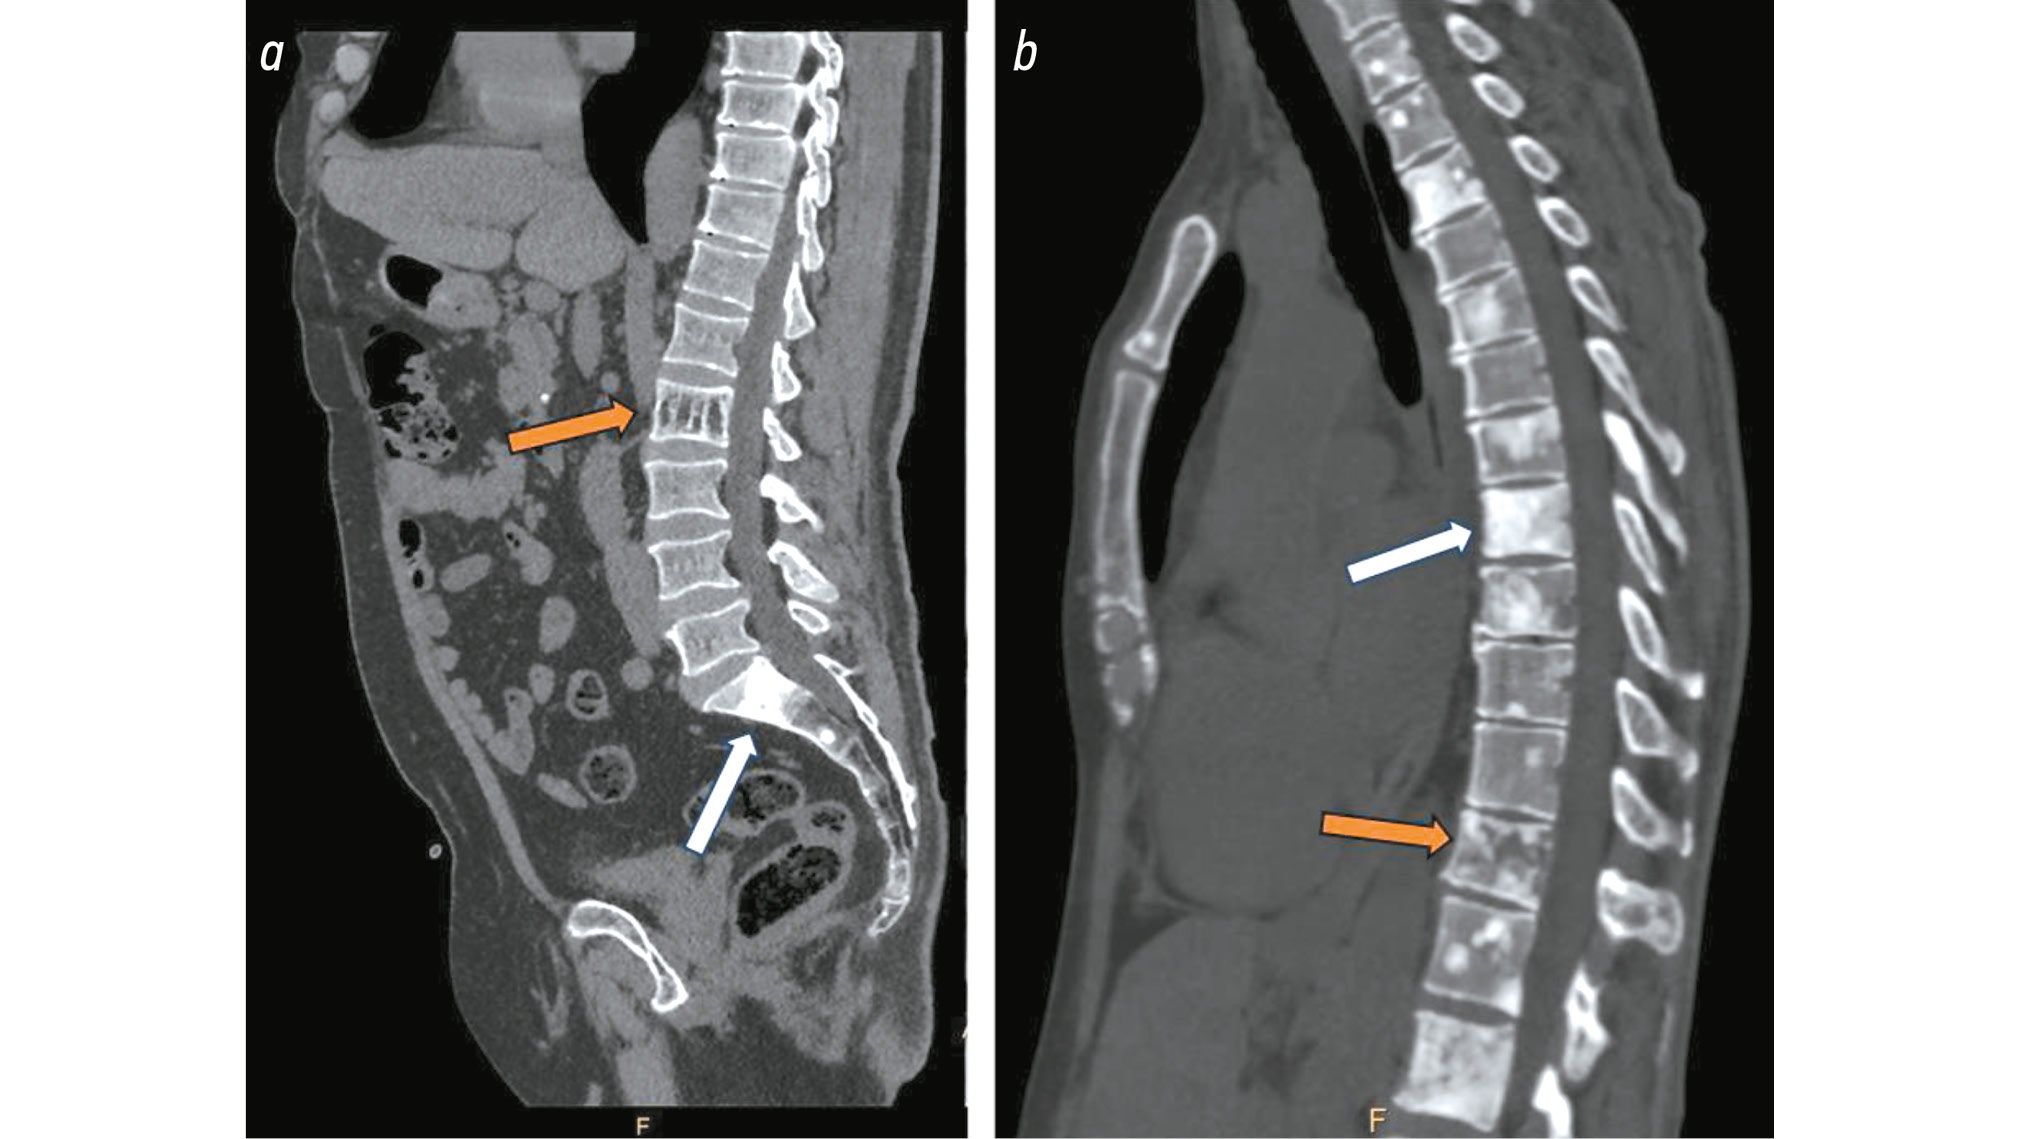

One of the primary benefits of MSCT is the short scan time, which is especially essential in emergency circumstances where patients suddenly develop pain. This technique identifies fractures caused by existing secondary bone lesions and spinal nerve compression [21, 23]. However, due to the limited contrast uptake by soft tissues, MSCT is seldom used as a primary diagnostic tool in PC. It is more typically employed for the detection of distant metastases and for biopsy guidance [19]. This technique determines the structure of the bone metastases and the extent of bone destruction. Additionally, it enables the use of extra image processing techniques for metal artifact reduction in the imaging-based evaluation of surgical hardware [23]. The formation of reactive sclerosis during treatment and the progression of osteoblastic metastases appear to be similar on MSCT scans (by increased lesion density). Because of this characteristic of bone metastases, the RECIST 1.1 criteria categorize these lesions as non-measurable (Fig. 1) [24]. Radiomics facilitate the quantitative assessment of lesions [25].

Fig. 1. a, Lumbar spine MSCT, sagittal plane: osteoblastic lesions observed in the S1 and S2 vertebral bodies (white arrow), hemangioma in the L2 vertebral body (orange arrow); b, thoracic spine MSCT, sagittal plane: osteoblastic lesions in thoracic vertebral bodies (white arrow), mixed lesion noted in the Th12 vertebral body (orange arrow).